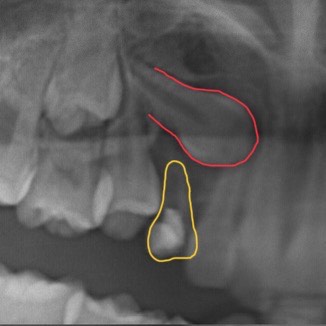

例えば、このレントゲンをご覧ください。

上あごの前から3番目の大人の歯(犬歯・赤色)が骨の中に埋まったままになり(埋伏)、前から3番目の子どもの歯(乳犬歯・黄色)が抜け残っている状態です。

このまま放置すると埋伏した犬歯は生えてこないばかりか、周囲の骨や他の歯の根を溶かし始める危険があります。

埋伏した歯を生やすためには、矯正治療で歯の向きを正しい方向へ動かすことが必要です。